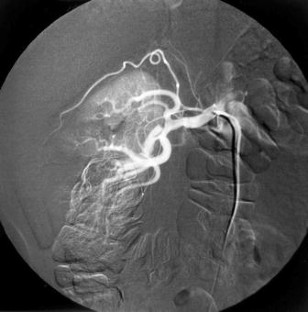

Renal infarction is a rare cause of acute abdominal and flank pain. Whether it occurs due to thrombosis or embolism, the occlusion of the renal arteries always results in renal infarction. Cigarette smoking is a known risk factor for arterial thrombosis. Both vasoconstrictor and pro-thrombotic effects of smoking lead to arterial thrombosis. Herein, we report a case of acute renal infarction in a heavy smoker. The definite diagnosis was made by contrast-enhanced abdominal computerized tomography and renal arteriography.

Fig. 2